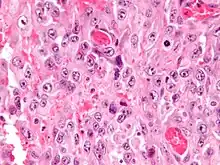

| Micrograph of an epithelioid sarcoma. H&E stain. | |

Histologically, epithelioid sarcoma forms nodules with central necrosis surrounded by bland, polygonal cells with eosinophilic cytoplasm and peripheral spindling.[3] Epithelioid sarcomas typically express vimentin, cytokeratins, epithelial membrane antigen, and CD34, whereas they are usually negative for S100, desmin, and FLI1 (FLI-1).[3] They characteristically lack the protein INI1 (see below). Epithelioid sarcomas typically stain positive for CA125.[4]

Intermed. mag.

Intermed. mag. High mag.